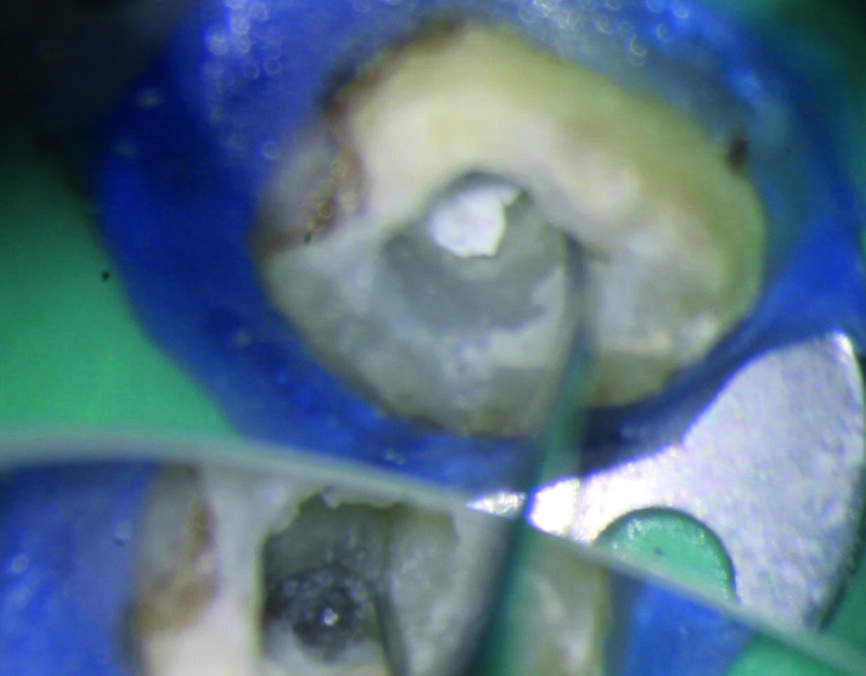

Une anesthésie locale est réalisée, la dent est isolée avec une digue et la cavité d’accès est préparée. L’obturation en gutta-percha située en coronaire du fragment est éliminée au moyen d’une pièce à main sonique (SONICflex 2003 L, KaVo) et de limes Micro Type D (MANI), sous examen microscopique direct (Fig. 2). Ensuite, une plate-forme de travail périphérique est préparée au niveau de l’extrémité coronaire du fragment. Pour ce faire, une fraise Gates–Glidden modifiée de taille 3 (MANI ; Fig. 3) est utilisée à basse vitesse de rotation de 300 trs/min et dirigée apicalement jusqu’à entrer en contact avec le fragment instrumental fracturé. La procédure est réalisée dans chaque canal (Figs. 4 et 5). La plate-forme doit être légèrement plus large que le diamètre coronaire du fragment (Fig. 6). Un espace est créé autour du fragment au moyen d’une pièce à main sonique (SONICflex Quick 2008 L, KaVo) munie d’un insert Endo Clean de taille 25 (portion coronaire exposée sur 2 mm). Au cours de cette étape, le même insert est utilisé pour émousser la partie active (lames) de l’instrument fracturé, afin d’éviter d’endommager la boucle du fil métallique (Figs. 7a et b) qui servira de lasso.

Fig. 2 : Lime Micro Type D à utiliser avec SONICflex 2003 L et adaptateur OSADA.

Fig. 4 : Création d’une plate-forme de travail avec une fraise Gates–Glidden modifiée de taille 3.